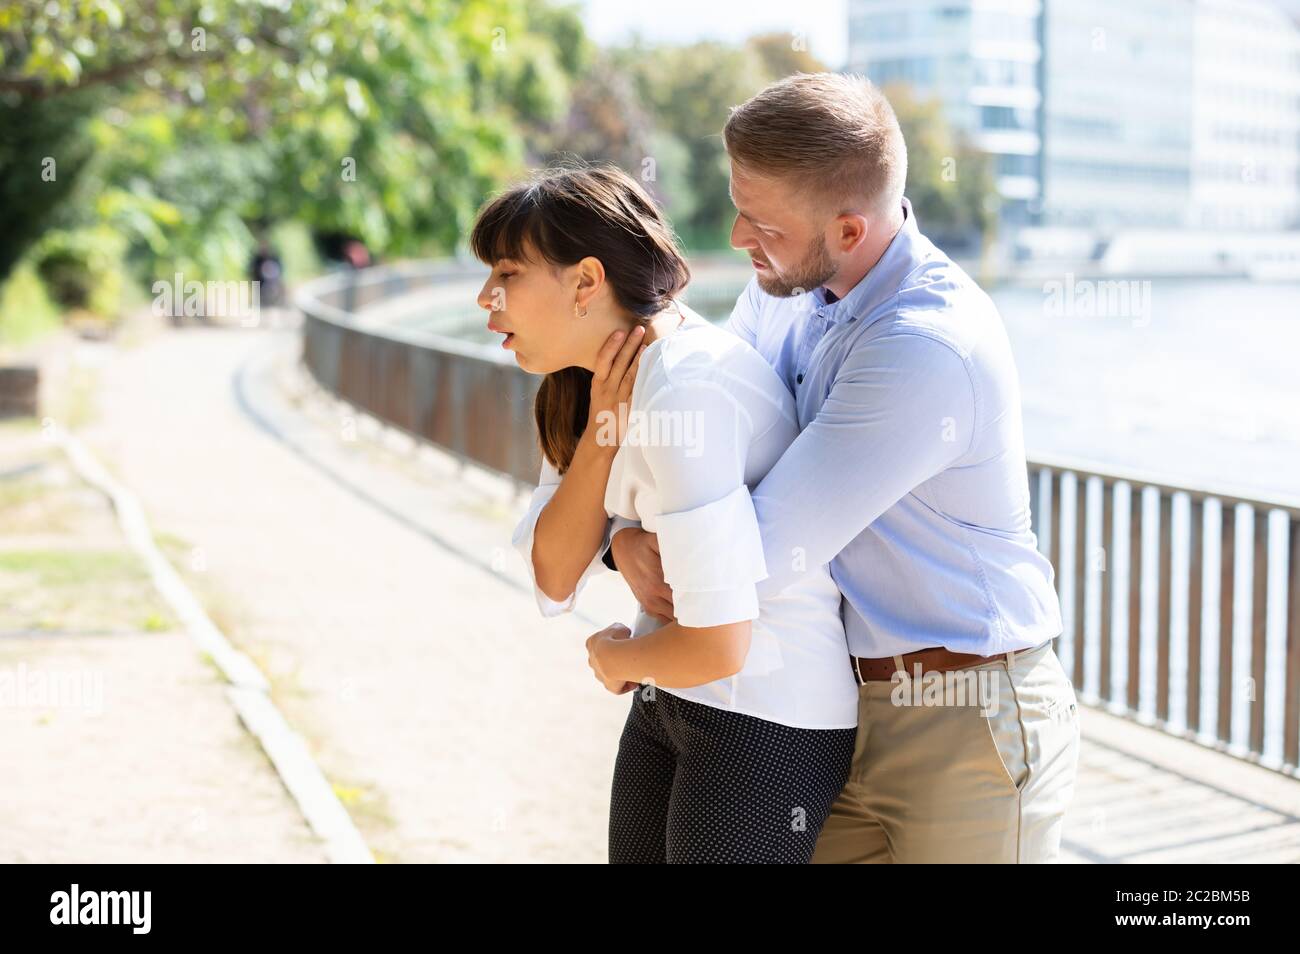

Man Helping Choking Woman To Expel A Trapped Object From Airway. Heimlich Maneuver Stock Photohttps://www.alamy.com/image-license-details/?v=1https://www.alamy.com/man-helping-choking-woman-to-expel-a-trapped-object-from-airway-heimlich-maneuver-image327215476.html

Man Helping Choking Woman To Expel A Trapped Object From Airway. Heimlich Maneuver Stock Photohttps://www.alamy.com/image-license-details/?v=1https://www.alamy.com/man-helping-choking-woman-to-expel-a-trapped-object-from-airway-heimlich-maneuver-image327215476.htmlRF2A09XK0–Man Helping Choking Woman To Expel A Trapped Object From Airway. Heimlich Maneuver

Man Helping Choking Woman To Expel A Trapped Object From Airway. Heimlich Maneuver Stock Photohttps://www.alamy.com/image-license-details/?v=1https://www.alamy.com/man-helping-choking-woman-to-expel-a-trapped-object-from-airway-heimlich-maneuver-image362904342.html

Man Helping Choking Woman To Expel A Trapped Object From Airway. Heimlich Maneuver Stock Photohttps://www.alamy.com/image-license-details/?v=1https://www.alamy.com/man-helping-choking-woman-to-expel-a-trapped-object-from-airway-heimlich-maneuver-image362904342.htmlRF2C2BM5A–Man Helping Choking Woman To Expel A Trapped Object From Airway. Heimlich Maneuver

Man Helping Choking Woman To Expel A Trapped Object From Airway. Heimlich Maneuver Stock Photohttps://www.alamy.com/image-license-details/?v=1https://www.alamy.com/man-helping-choking-woman-to-expel-a-trapped-object-from-airway-heimlich-maneuver-image327215172.html

Man Helping Choking Woman To Expel A Trapped Object From Airway. Heimlich Maneuver Stock Photohttps://www.alamy.com/image-license-details/?v=1https://www.alamy.com/man-helping-choking-woman-to-expel-a-trapped-object-from-airway-heimlich-maneuver-image327215172.htmlRF2A09X84–Man Helping Choking Woman To Expel A Trapped Object From Airway. Heimlich Maneuver

Man Helping Choking Woman To Expel A Trapped Object From Airway. Heimlich Maneuver Stock Photohttps://www.alamy.com/image-license-details/?v=1https://www.alamy.com/man-helping-choking-woman-to-expel-a-trapped-object-from-airway-heimlich-maneuver-image362904343.html

Man Helping Choking Woman To Expel A Trapped Object From Airway. Heimlich Maneuver Stock Photohttps://www.alamy.com/image-license-details/?v=1https://www.alamy.com/man-helping-choking-woman-to-expel-a-trapped-object-from-airway-heimlich-maneuver-image362904343.htmlRF2C2BM5B–Man Helping Choking Woman To Expel A Trapped Object From Airway. Heimlich Maneuver